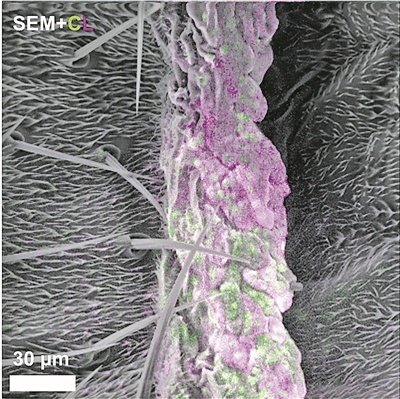

新成像技术能同步观测细胞精细结构

受真菌感染果蝇的多色电子显微镜图像。图中可见真菌的细胞核(绿色)、线粒体(紫色)以及果蝇表面的精细结构。图片来源:物理学家组织网 美国哈佛大学科学家研制出一种新型成像技术。这是一种多色显微镜技2026-03-05 -